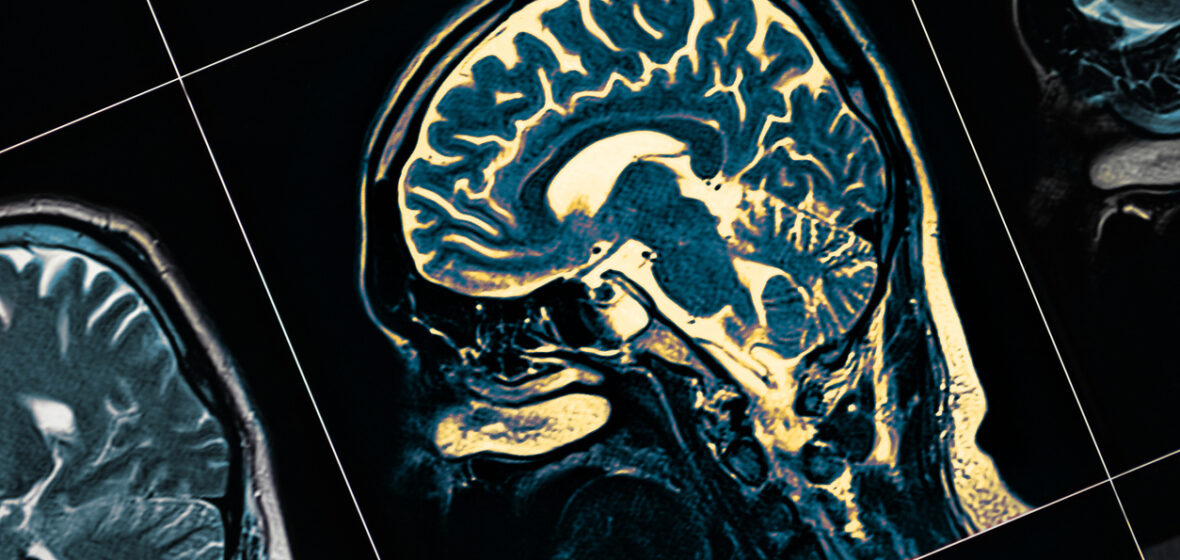

- Young onset dementia refers to any type of dementia where symptom onset occurs before the age of 65. Behaviour changes that contribute to legal problems in midlife—criminal offending, relationship breakdown or poor job performance—should prompt consideration of young onset dementia.

What Michael and his family don’t yet understand is that these behavioural changes are symptoms of young onset dementia.